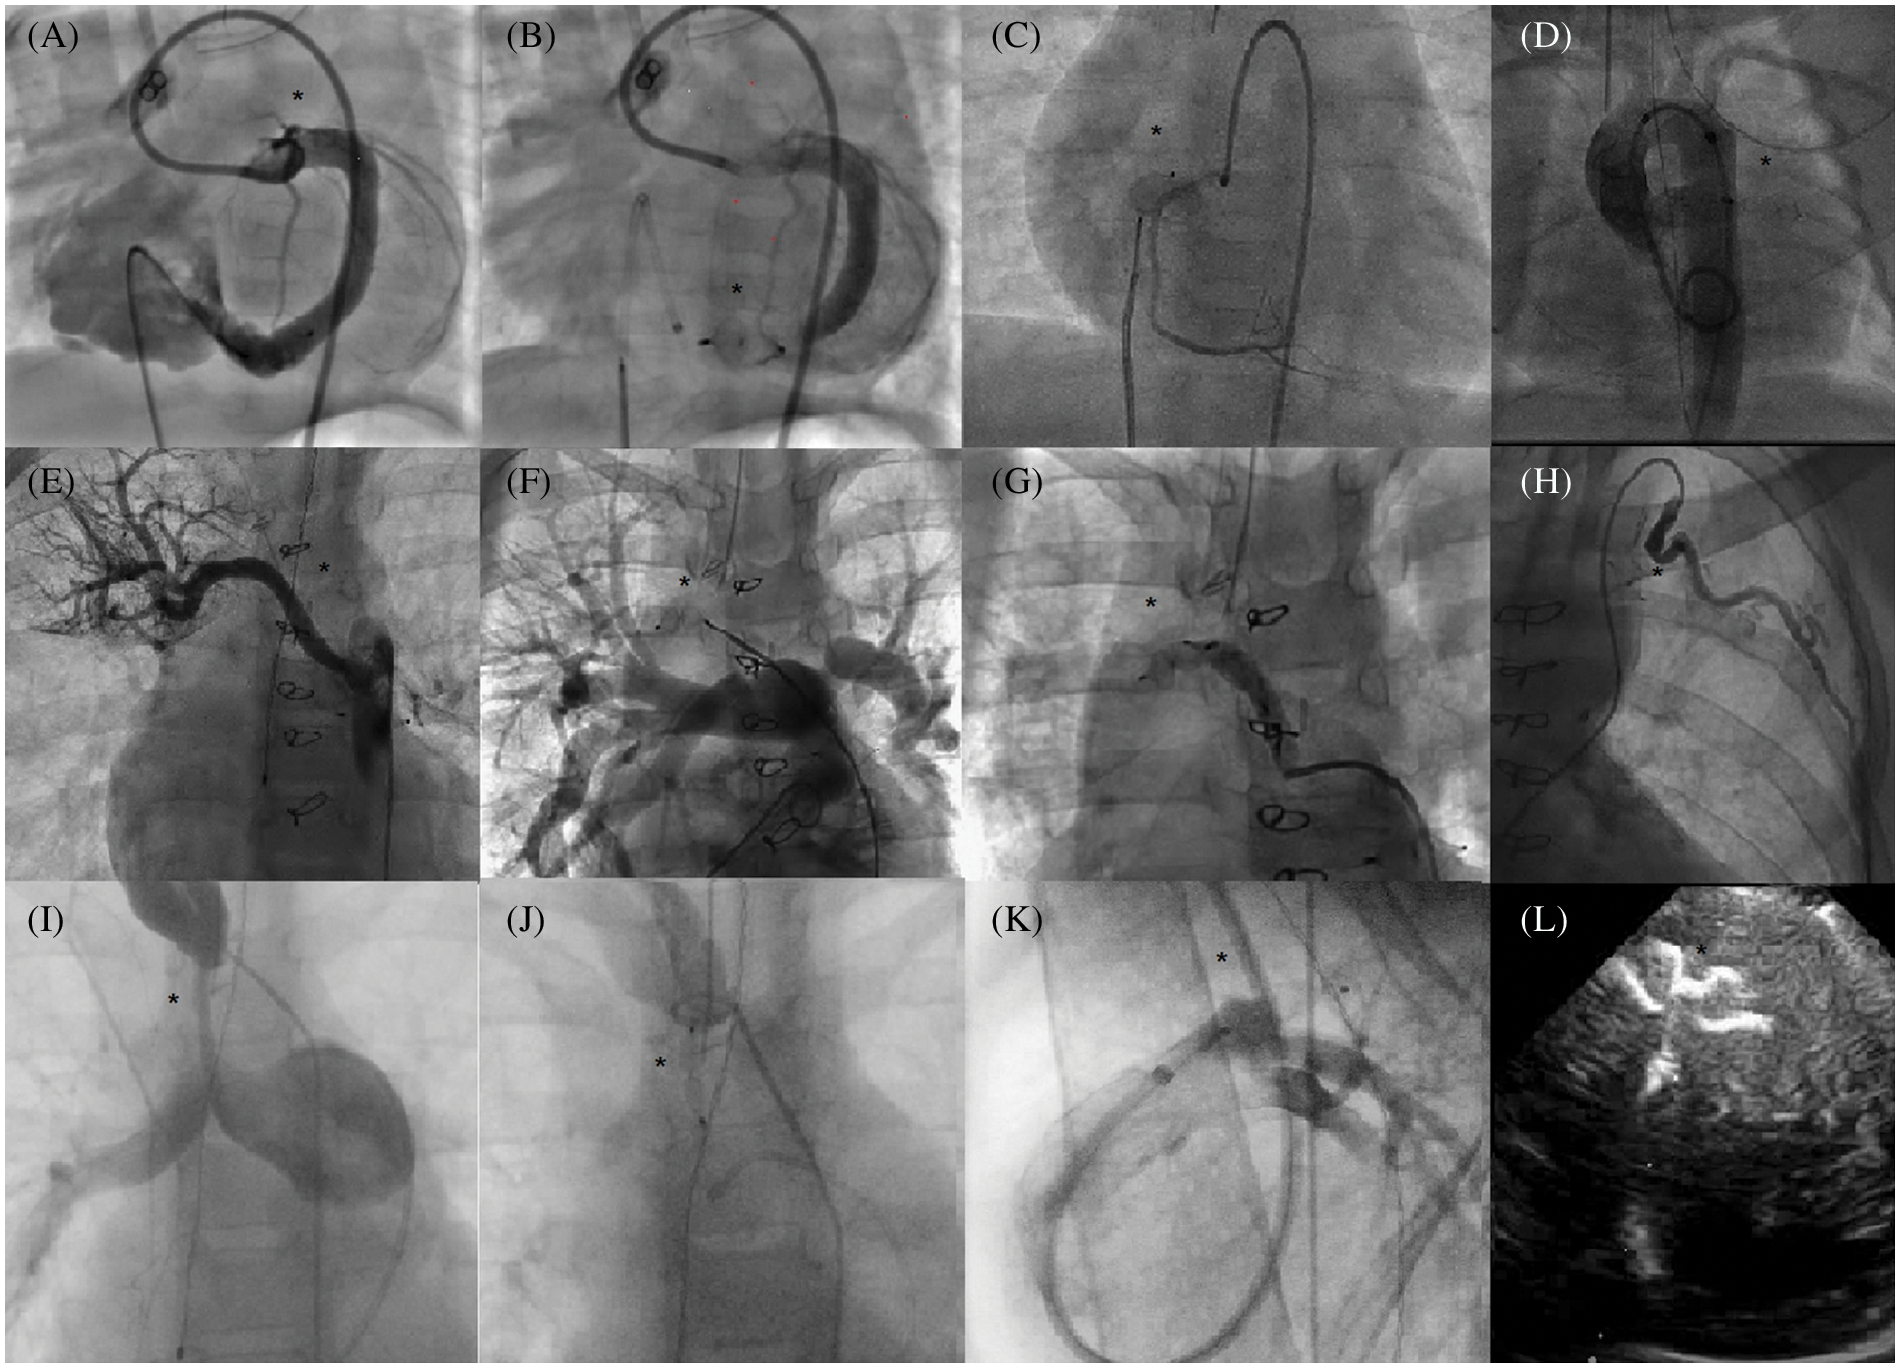

A wide variety of procedures were carried out throughout the study period (Fig. 3).

Figure 3: Use of AVP IV for multiple occlusions in children Angiograms (area of interest is designated by a black star). A, B: Retrograde CAF (congenital artery fistulae) closure (circumflex artery to right ventricle). C: Retrograde CAF closure (right coronary to right atrium). D: Rescue anterograde closure of left aortic sinus to left atrium fistulae. E, F, G: Selective embolization of a non-communicating aorto-pulmonary collateral. H: Selective embolization of an arterial collateral from the left internal mammary artery. I, J: Percutaneous occlusion of a right modified Blalock anastomosis. K: Venous closure of a patent ductus arteriosus via the jugular vein. Echocardiogram (Apical view) L: Muscular ventricular septal defect closure

Successful closures of anomalous or aberrant systemic arterial supply to a lung segment was achieved using 18 AVP IV and 2 AVP II. Six uncomplicated closures of single or multiple congenital artery fistulae (CAF) using 6 to 8 mm AVP IV in infants and neonates were also completed, for which delayed post-procedure angiograms demonstrated the absence of residual shunt or coronary thrombosis. The effective closures of 2 peri-membranous Ventricular Septal Defects (VSD) with aneurysm (AVP II) as well as 1 postoperative VSD (AVP IV) and 2 muscular VSDs (AVP IV, Fig. 3L) were also achieved. The miscellaneous group included single procedures such as closure of fenestration (Fontan circulation), closure of congenital fistula of the left aortic sinus to the left atrium (CAF “like”), ductus venosus closure, or left hepatic artery occlusion.